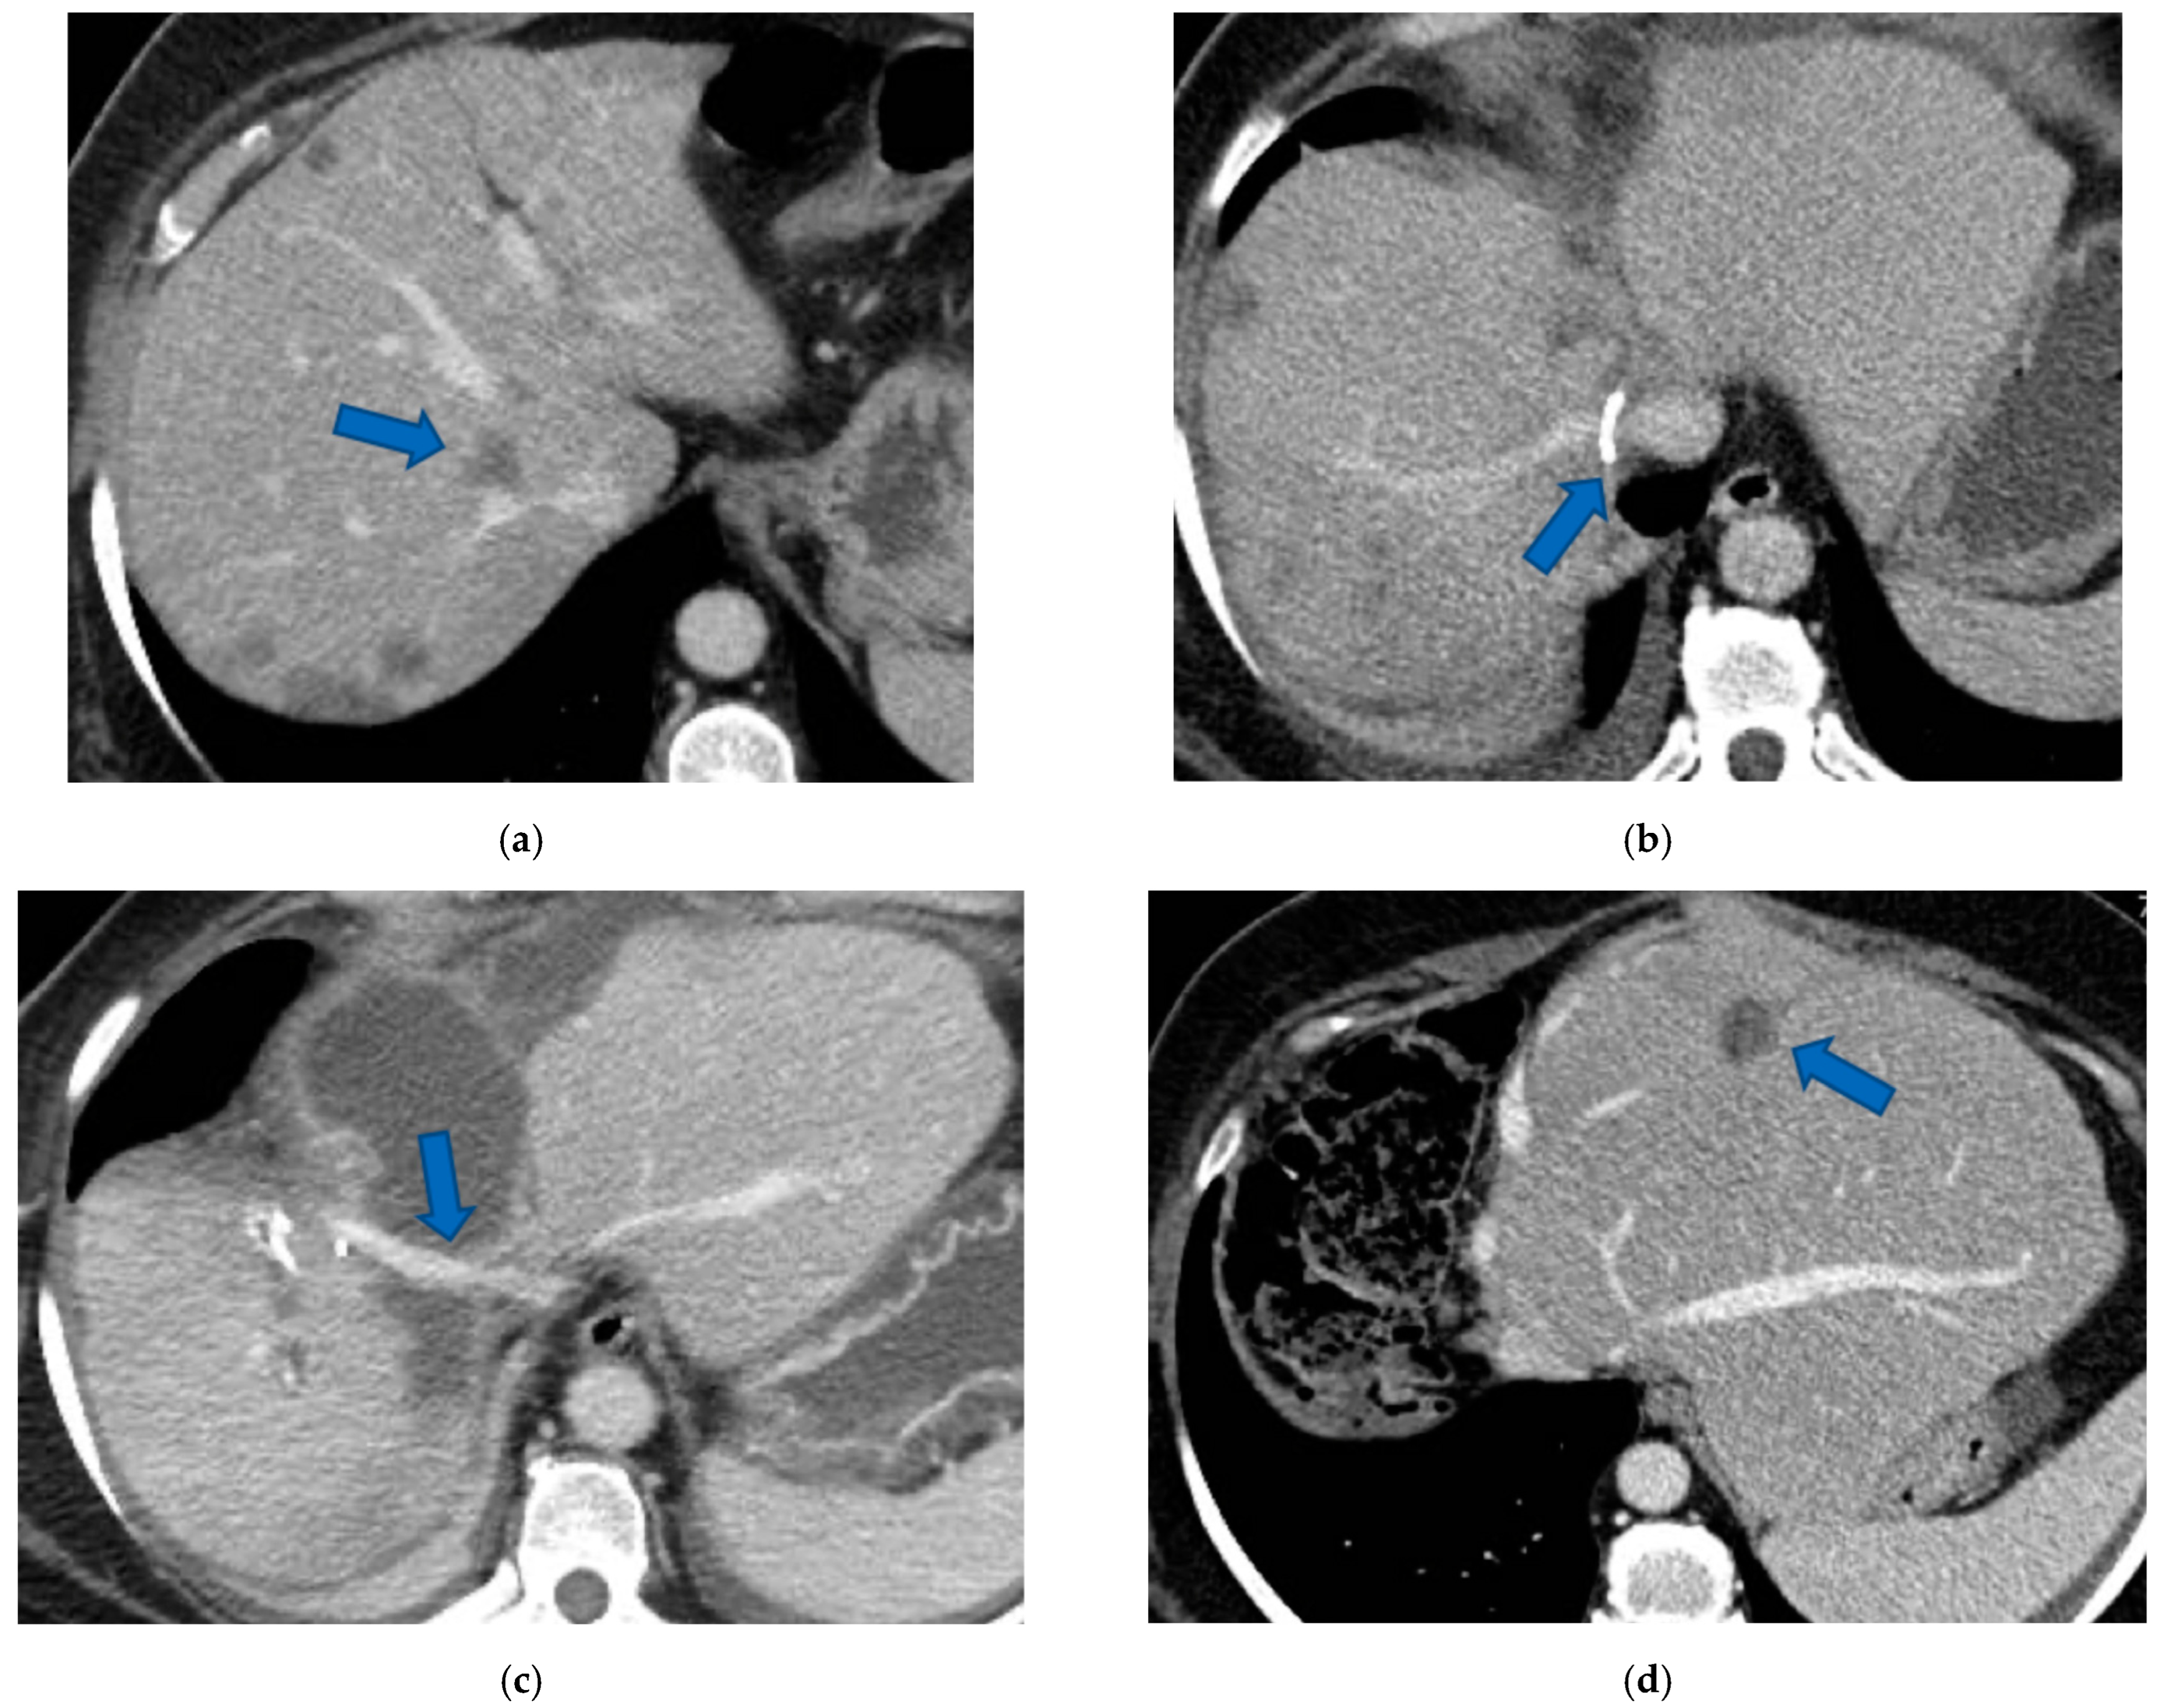

In four cases the Spiegel lobe was preserved. At the first stage (MLP) MHV was resected in four cases, preserved in deportalized liver in the case of FLR = part of S6/S7 and reconstructed with an end-to-lateral anastomosis with LHV (FLR = S4b/S2/Spiegel lobe) in one case. In two patients (FLR 15% = part of S4/S2 and Spiegel lobe; FLR 7% = part of S2/S3) FLR volume was deemed inadequate after the first step of e-ALPPS (FLR 29% and 28%, 15 and 17 days after the first stage), daily liver growth after the first stage was 21 mL/day in the first 8 days and 8 mL/day in the subsequent 7 days in one case and 19 mL/day in the first 17 days in the other (in the latter, growth kinetic cannot be evaluated during the first week since CT was not performed). Intermediate stage of partial resection of the deportalized liver was performed (in both cases resection of S5-S8, in one case en-bloc with RHV which was reconstructed with an end-to-end anastomosis). Seven days after the intermediate stage FLR volume increased up to 39% and 41% with a daily growth of 18 mL/day and 25 mL/day. The third stage to complete the ALPPS procedure was performed (23 and 27 days after the first stage) resecting the last part of deportalized liver (S6/S7). In both cases the left hemicolectomy was associated to third step of staged e-ALPPS (see Figure 10, Figure 11, Figure 12 and Figure 13).

In a case of e-ALPPS an intermediate stage of PSH of the deportalized liver was necessary (due to inadequate FLR volume of S2/S3 18 days after the first stage), at the intermediate stage S5/S8 were resected en-bloc with RHV which was reconstructed with an end-to-end anastomosis (Figure 11).

To date, in our institution, liver function evaluation with 99mTc-mebrofenin hepatobiliary scintigraphy is not available and liver volume is still the way to determine the adequate FLR [32]. In two cases of e-ALPPS (Figure 10, Figure 11, Figure 12 and Figure 13), adequate FLR was not achieved after the first stage despite MHV resection, which is considered a procedure accentuating FLR volume hypertrophy [33]. Our MDT, observing FLR volume increase after the resection of embolized liver in PS-TSH with SS-PVE, proposed the partial resection of deportalized liver as a boost for FLR regeneration up to the adequate volume. We observed for the first time a FLR volume increase beyond the classical ALPPS technique [6], which is considered the most powerful liver augmentation technique [34]. The regeneration observed is completely independent of the venous system and it is not possible to advocate the same mechanism of PVE, PVL or liver deprivation. The arterial system is most probably responsible for the observed volume increase and this is supported by Zhuo et al., who observed the same in a case of hepatic arterial infusion chemotherapy and arterial embolization in the deportalized liver with a huge HCC and inadequate FLR hypertrophy one month after stage 1 ALPPS [35].